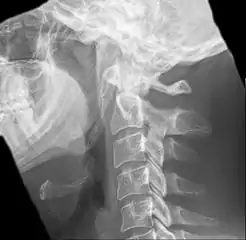

Radiograph, lateral view showing elongated stylohyoid process and stylohyoid ligament ossification

Radiograph, lateral view showing joint-like formation in ossified stylohyoid ligament

Imaging is important and is diagnostic. Visualizing the styloid process on a CT scan with 3D reconstruction is the suggested imaging technique.[11] The enlarged styloid may be visible on an orthopantogram or a lateral soft tissue X ray of the neck.